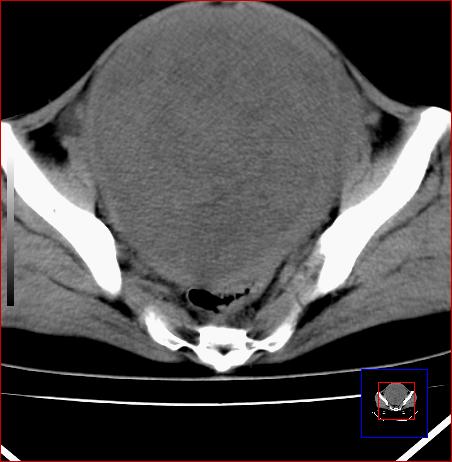

标题: CT15141:子宫肌瘤还是卵巢肿瘤 [打印本页]

标题: CT15141:子宫肌瘤还是卵巢肿瘤

腹部包块1年余,近两月明显增大,月经量多

病灶呈实性包块,边界清晰,似与子宫分界不清,考虑:子宫肌瘤

子宫体积增大,内密度不均匀。边缘清晰。考虑子宫肌瘤。